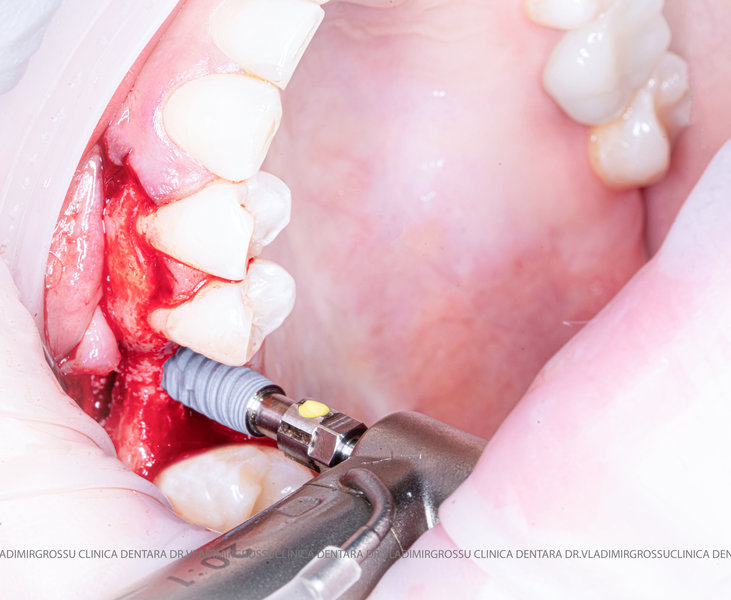

După extracția dentară, în intervalul de 6-12 luni, osul alveolar suferă un proces natural de remodelare, ceea ce conduce la scăderea volumului osos prin rezorbție. De aceea, inserția implantului dentar este ideală imediat după extracție sau, cel târziu, în primele 3-4 luni după aceasta.Scopul procedurilor de adiție osoasă este refacerea fundației osoase necesare pentru stabilizarea corectă a implantului dentar. Pentru ca un implant să reziste în timp la forțele masticatorii, este nevoie de o bază osoasă solidă și sănătoasă.

Termenii „adiție osoasă” și „augmentare osoasă” au același scop, diferența fiind că adiția osoasă presupune aplicarea materialului osos pe o suprafață plană, în timp ce augmentarea implică inserția materialului într-o cavitate, cum este cazul sinusului maxilar (procedura de sinus lifting).

Procesul de refacere osoasă este complex, însă, simplificat, se bazează pe faptul că osul adăugat se integrează treptat, fiind înlocuit parțial cu os natural, oferind astfel suportul necesar implantului.